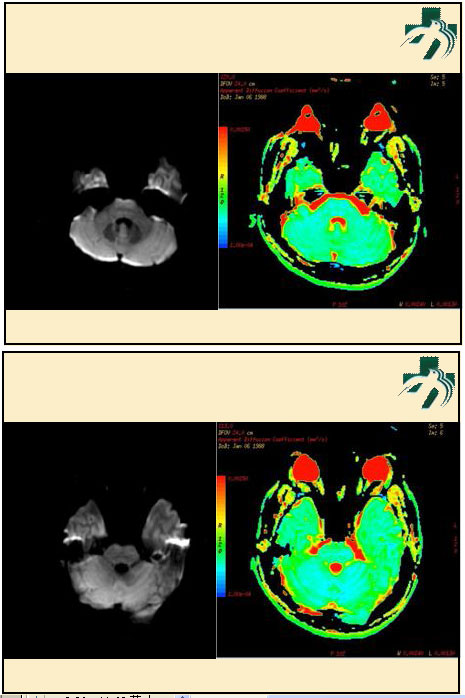

奴卡氏菌感染

第九期三博

读片会

病例之四

北京协和医院 提供

男性,22岁。自觉虫咬后皮疹、肢体麻木4月